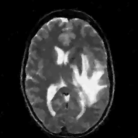

We study the performance of the proposed algorithms as a function of acceleration in the presence of noise in Fig. 3. We used a 512×512512512512\times 512 MRI brain image, sampled using a random sampling operator at different acceleration factors (R = 2.5, 4, 6, 8, 10 and 202020). The measurements were contaminated with complex white Gaussian noise of σ=10.2𝜎10.2\sigma=10.2. The PSNR and SNR as a function of accelerations of this experiment are plotted in Fig. 3, where we compare our method against DLMRI and TV. We observe that the proposed scheme provides a consistent improvement in the presence of noise.

The reconstructions of an ankle image from its 4 fold Cartesian undersampled Fourier data, corrupted with zero mean complex Gaussian noise with a standard deviation σ=10𝜎10\sigma=10, are shown in Fig. 5. This is a really challenging case since the 1-D downsampling pattern is considerably less efficient than the 2-D random pattern used in the previous experiment. We observe that the non-local algorithm provides better reconstructions than the other schemes. Specifically, the TV scheme results in patchy artifacts. The DLMRI scheme results in blurring and loss of details close to the heel. The details are relatively better preserved close to the finger since there are no structures above or below it that aliases to it. By contrast to the classical algorithms, the degradation in performance of the non-local algorithm is comparatively small. The quantitative comparisons of the algorithms on this setting using different images are shown in the top section of Table IV.

The reconstructions of a 256×256256256256\times 256 brain image from its radial samples acquired with a 40 spoke trajectory are shown in Fig. 6. The measurements are corrupted with zero mean complex Gaussian noise of standard deviation σ=18.8𝜎18.8\sigma=18.8. All methods result in loss of subtle image features since the acceleration factor and the noise level are high. We observe that the NLS scheme provides better recovery than the competing methods. The quantitative results in this setting for various MR images are shown in the bottom section of Table IV. We observe that the SNR improvement offered by NLS over the other methods are not as high as in the previous cases, mainly due to the considerable noise in the data and the high acceleration.

Refer to caption

(a) PSNR vs Accelerations

(b) SNR vs Accelerations

Figure 3: SNR and PSNR vs Acceleration. We used a 512×512512512512\times 512 MRI brain image, sampled using a random sampling operator at different acceleration factors (R=2.5,4,6,8,10 and 20). The measurements were contaminated with complex white Gaussian noise of σ=10.2𝜎10.2\sigma=10.2. The SNR of the reconstructions obtained using the three algorithms are plotted. These results show that the NLS scheme is capable of providing better reconstructions at a range of accelerations. Specifically, it provides a consistent improvement of 0.5-9 dB in SNR/PSNR over the other algorithms.

(a) Original

(b) DLMRI,SNR=17.46

(c) TV,SNR=17.43

(d) NLS,SNR=18.46

(e) Sampling pattern

(f) DLMRI error

(g) TV error

(h) NLS error

Figure 6: Comparison of the algorithms in the presence of noise. We consider the recovery of a 256×256256256256\times 256 original MRI brain image from its radial trajectory with 40 spokes, contaminated by Gaussian noise with standard deviation σ=18.8𝜎18.8\sigma=18.8. The error images are magnified by a scale of 5 fold for the best visibility. This is a challenging case due to the high undersampling factor and high measurement noise. We observe that the NLS scheme provides the best overall reconstructions.